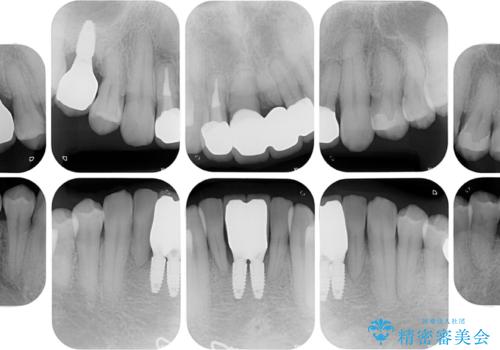

矯正治療を行いながら、欠損部はインプラントによる補綴治療を希望されたため、補助装置を用いたワイヤー矯正によりスペースを確保しながら歯列を整え、適宜インプラントを埋入していくこととしました。

下顎前歯にインプラントを2本埋入するのは非常に困難であり、どうしても歯肉位置に土台の金属色が見えてしまう仕上がりとなりました。無理をせずに1本のみの埋入とするか、ブリッジを提案しましたが、患者様の強い希望により、2本埋入することとなり、大変満足していただけました。